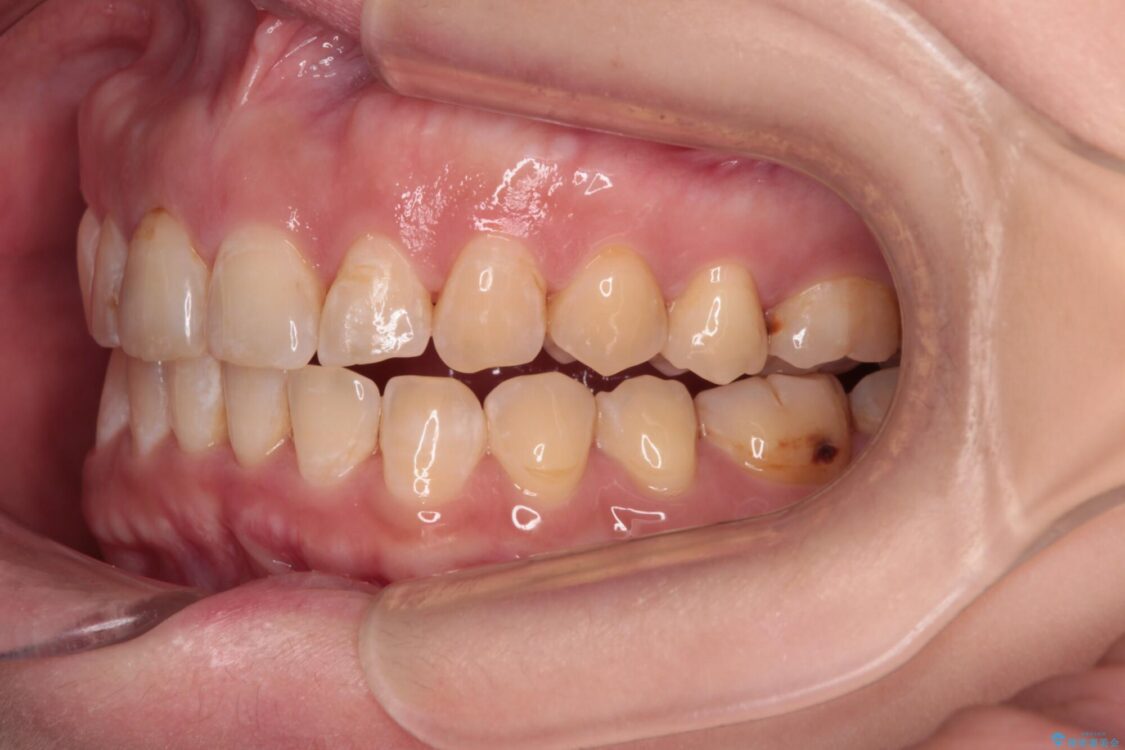

飛び出た上の前歯を気にして来院された患者様です。

奥歯の咬み合わせは、上顎歯列が理想的な一よりも数mm前方にある状態でした。

治療前

• 【モニター】飛び出た前歯を整えたい ワイヤー矯正治療 治療前画像